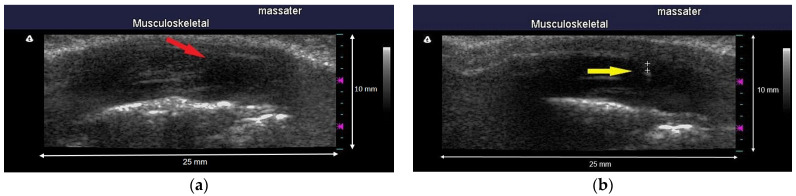

Morphological data on the MTrPs of masticatory muscles were mainly acquired through ultrasonography (Terason t3000 Ultrasound System, Ormond Beach, FL, USA). All ultrasonography evaluations performed in this study were performed by a single assessor who was familiar with ultrasonography operation and interpretation and was blinded to the grouping status of the tested animals. After the location of an MTrP on a rat was determined through palpation, a 7–12 MHz linear array transducer (Terason 12HL7, 25 mm hockey stick style, 128 elements) was placed on the masseter muscle parallel to its upper jaw with minimal pressure applied. Ultrasonography was conducted at a focal length range of 0.3–1.0 cm and an image depth of 1 cm. In our pilot study, the EPN locations detected using the EMG needle were scanned by performing an ultrasound, and the identified muscle nodules were mostly revealed to be hypoechoic (Figure 2). Therefore, the assessor determined that the hypoechoic nodules were MTrPs, captured the relevant images, and recorded them for further analysis.

Figure 2.

(a) The myofascial trigger points are visualized as a hypoechoic region which the red arrow points to with an elliptical appearance in ultrasound imaging. (b) The ultrasound image shows both the needle tip and the myofascial trigger points as indicated by the yellow arrow in the picture. The location of the needle tip indicates the detection of continuous EPN; any nodule identified at this site is hypoechoic.